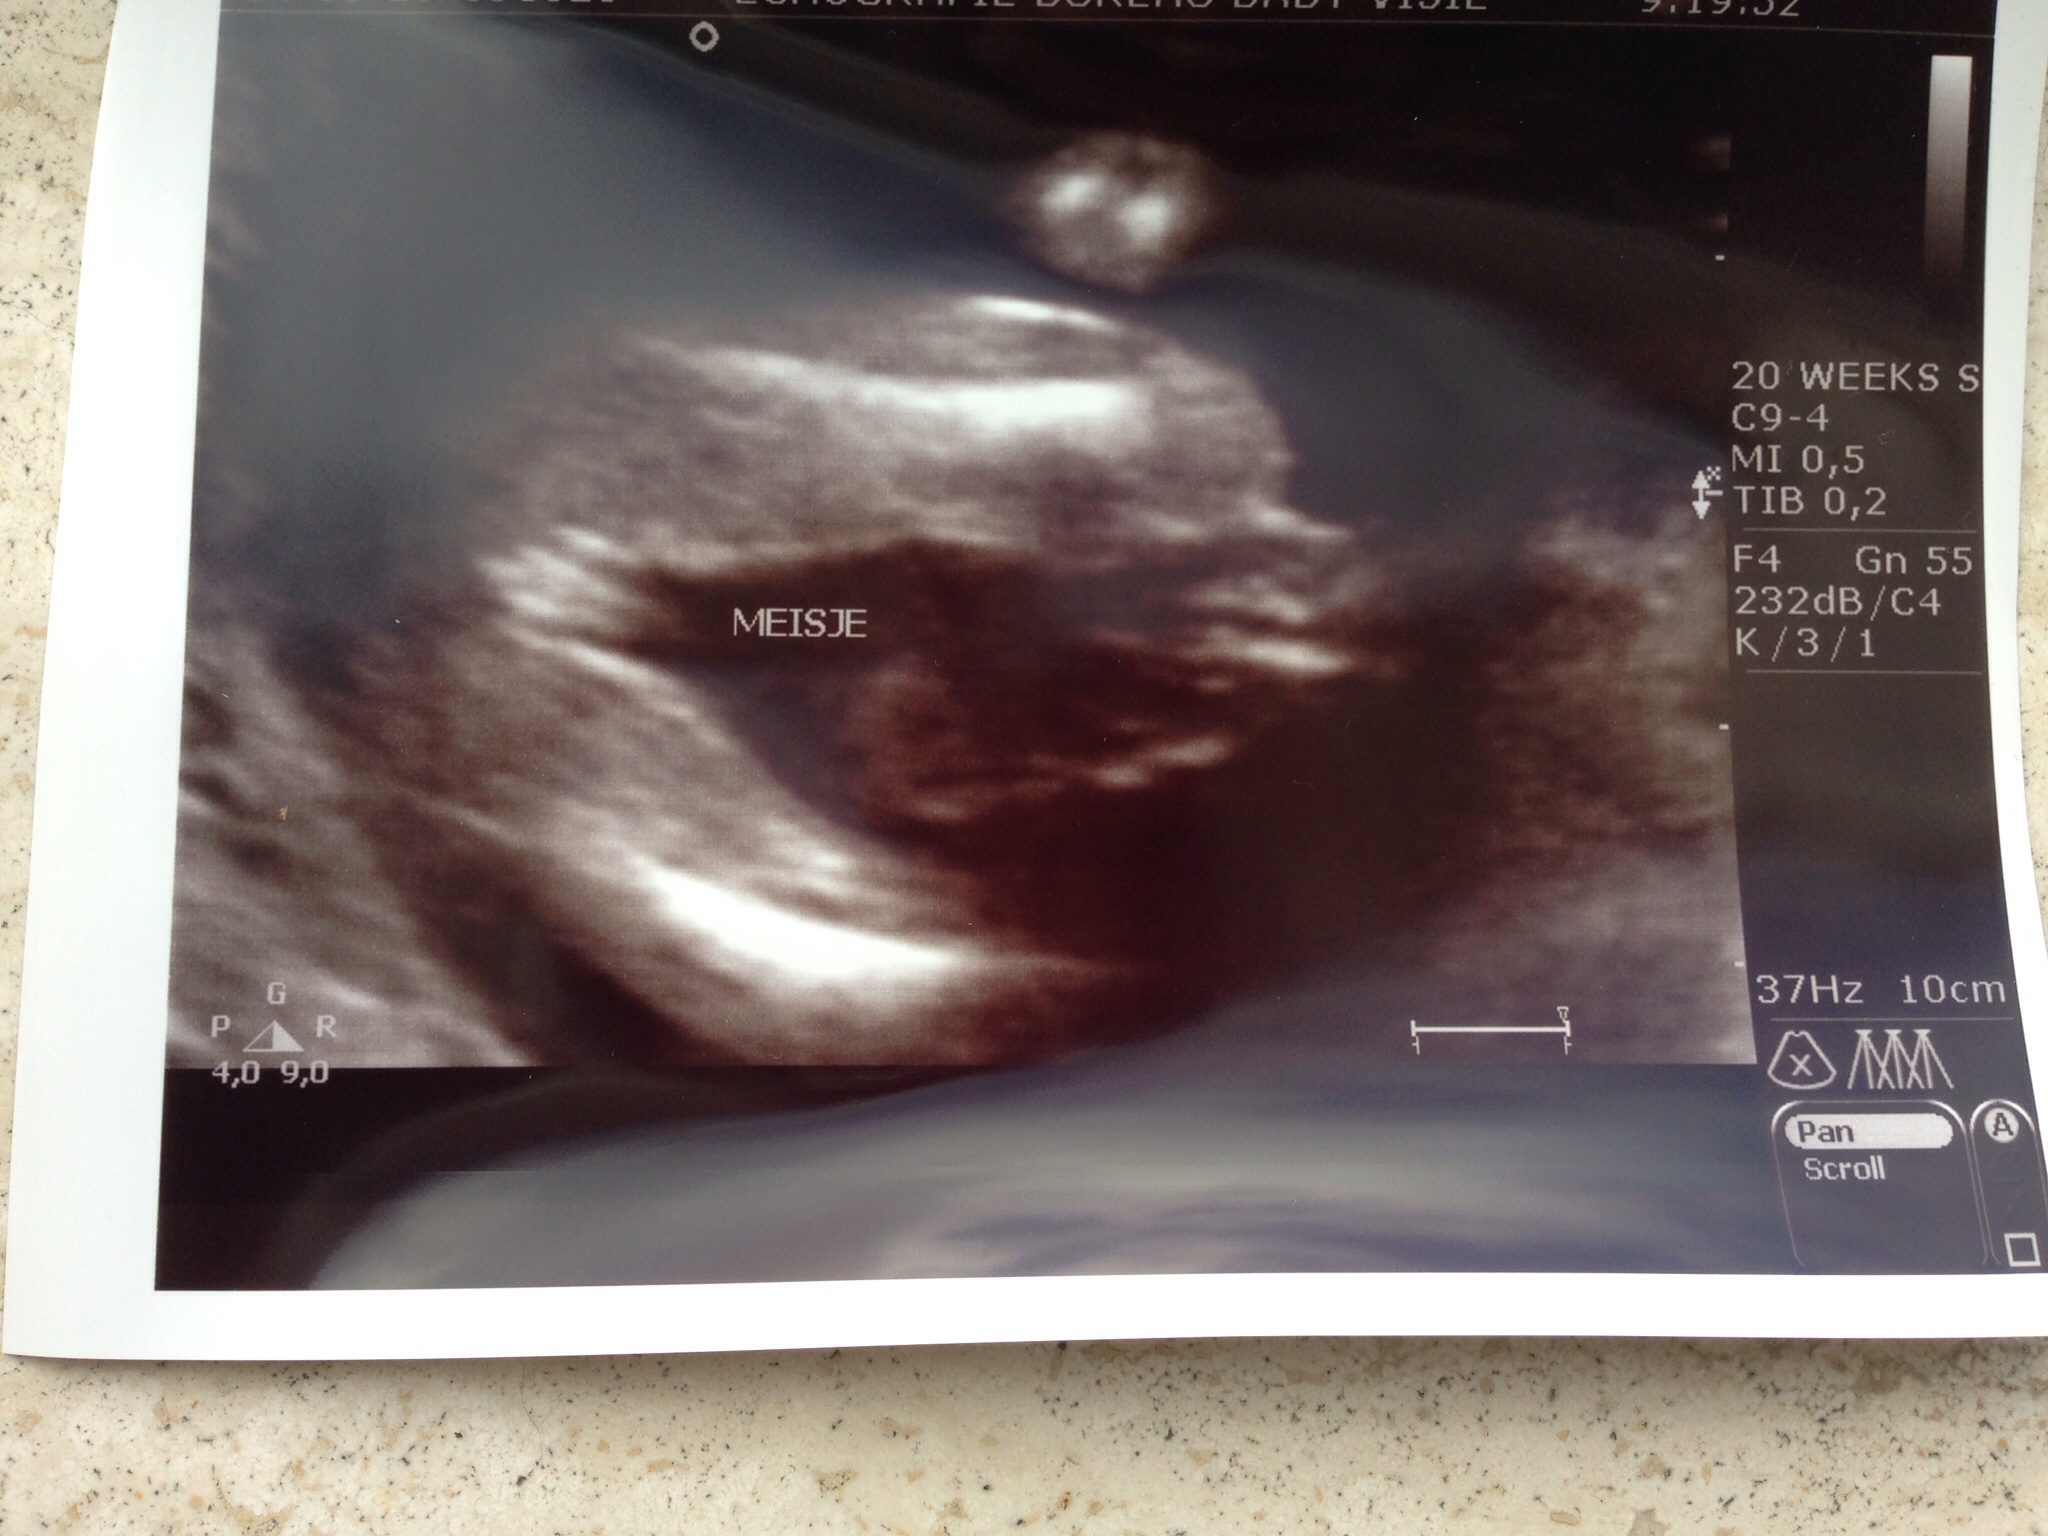

Update: still a little girl at my 20-week medical scan!

Also, my placenta isn't as high as they like to see( happens all the time), but to be sure they want another scan at 28 weeks. No concerns at all as this will never form a threat to babygirl..